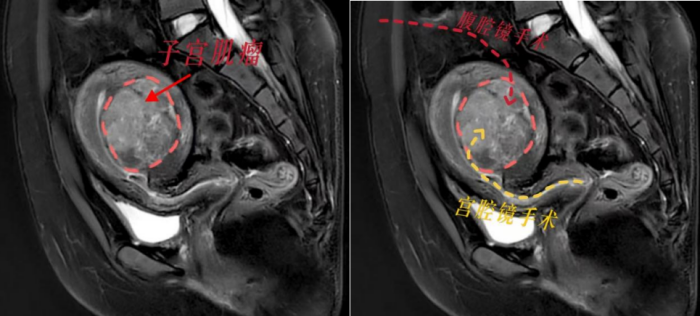

根据小丽的病情,香港马会app妇产科三区副主任魏馨分析,宫腔镜手术无需腹部切口,通过自然腔道进行,切除肌瘤无需切开子宫肌层,能最大程度保护患者生育力。但是根据子宫肌瘤诊治专家共识,像小丽这样的病例并不适合宫腔镜手术,因为手术风险极高,难以一次性切除干净,还可能引发水中毒、子宫内膜损伤等严重并发症。而如果选择腹腔镜下子宫肌瘤剥除术,就必须把子宫肌层完全切开,术后至少需要等待1年才能怀孕,且怀孕后子宫破裂的风险极大。这对于渴望成为母亲的小丽来说,无疑是沉重的打击。

面对患者强烈的生育需求,魏馨主任带领团队迎难而上,决心挑战“不可能”!经过反复研究病情和推敲手术方案,魏馨主任凭借丰富的临床经验和精湛的宫腔镜手术技巧,成功为小丽实施了高难度宫腔镜下子宫肌瘤切除手术。手术不仅一次性将肌瘤彻底切除,而且没有损伤子宫肌层和内膜,术中出血少,术后恢复快,未出现任何并发症。术后第2天,小丽便顺利出院,术后3个月即可备孕,重燃了她成为母亲的希望。